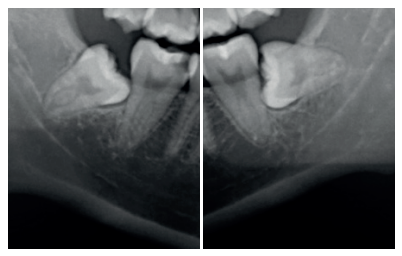

En la exploración radiográfica mediante radiografía panorámica se apreciaron ambos terceros molares inferiores retenidos, en una posición horizontal el 3.8 y mesioangular el 4.8 (Figura 1).

Se retiró la sutura de nuevo a la semana, y se realizaron revisiones a los 3 y 6 meses, donde se midió la profundidad de sondaje (Tabla). Se realizaron radiografías periapicales a los 3 meses (Figura 9) y a los 6 meses (Figura 10).

A los 6 meses se realizó una tomografía computarizada de haz cónico (Figura 11), para calcular la densidad ósea en el lado control (1372,33 Unidades Hounsfield) respecto al lado de estudio (1602,33 Unidades Hounsfield). Además, se comparó la altura a la cresta ósea en el lado control (disminución de 2,1 mm de altura ósea) respecto al lado de estudio (disminución de 0,9 mm de altura ósea).